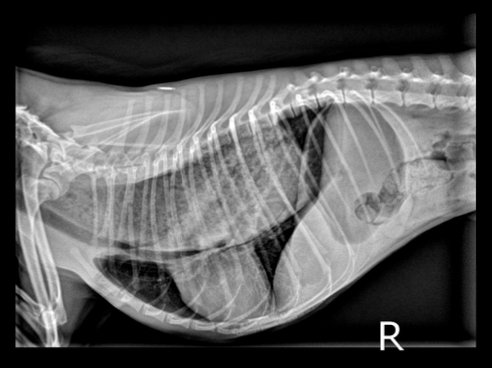

how is megaesophagus diagnosed?

-cervical and thoracic radiographs +/- oral contrast

-fluoroscopic swallow study